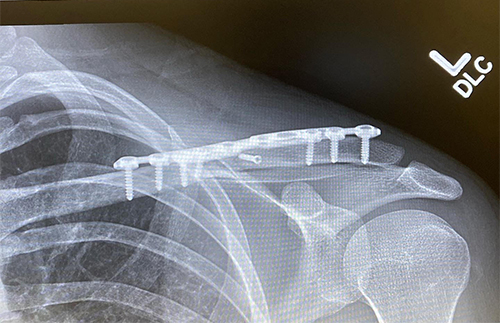

Figure 2

Clavicle, or "collar bone," fractures can happen from various mechanisms. They most commonly occur in the setting of motor vehicle and biking accidents or in a sports injury. They can occur when one falls onto an outstretched arm or gets direct contact to the shoulder area from the ground or another athlete. One typically feels a crack or pop with subsequent swelling in the area. It may be difficult to raise the arm after the injury due to pain. Figure 1 demonstrates a displaced clavicle fracture and Figure 2 demonstrates the clavicle after operative fixation with plate and screws.